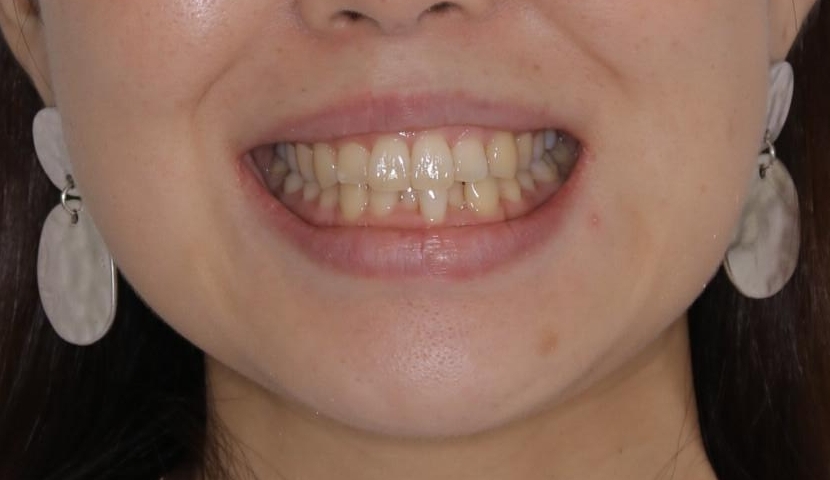

- 上下の前歯のがたつきが気になるとのことで来院されました。最短治療とインビザラインでの矯正治療をご希望されました。

前歯のがたつきを無くすためには、スペースを確保する必要があります。上の前歯のがたつきは軽度ながたつきのため、歯と歯の間を研磨をして、そのスペースを使い並べていきます。下の前歯は、1本前歯を抜いて研磨せずに、その抜歯したスペースを使い並べることになりました。

インビザライン・ライトにて矯正治療を行うことになりました。